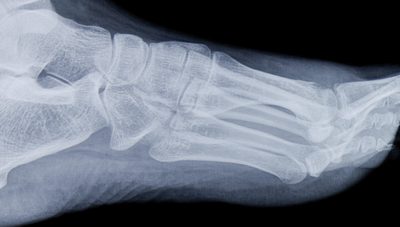

What Are Your Options If a Bone Injury in Your Foot Isn’t Healing

If you've damaged a bone in your foot,...